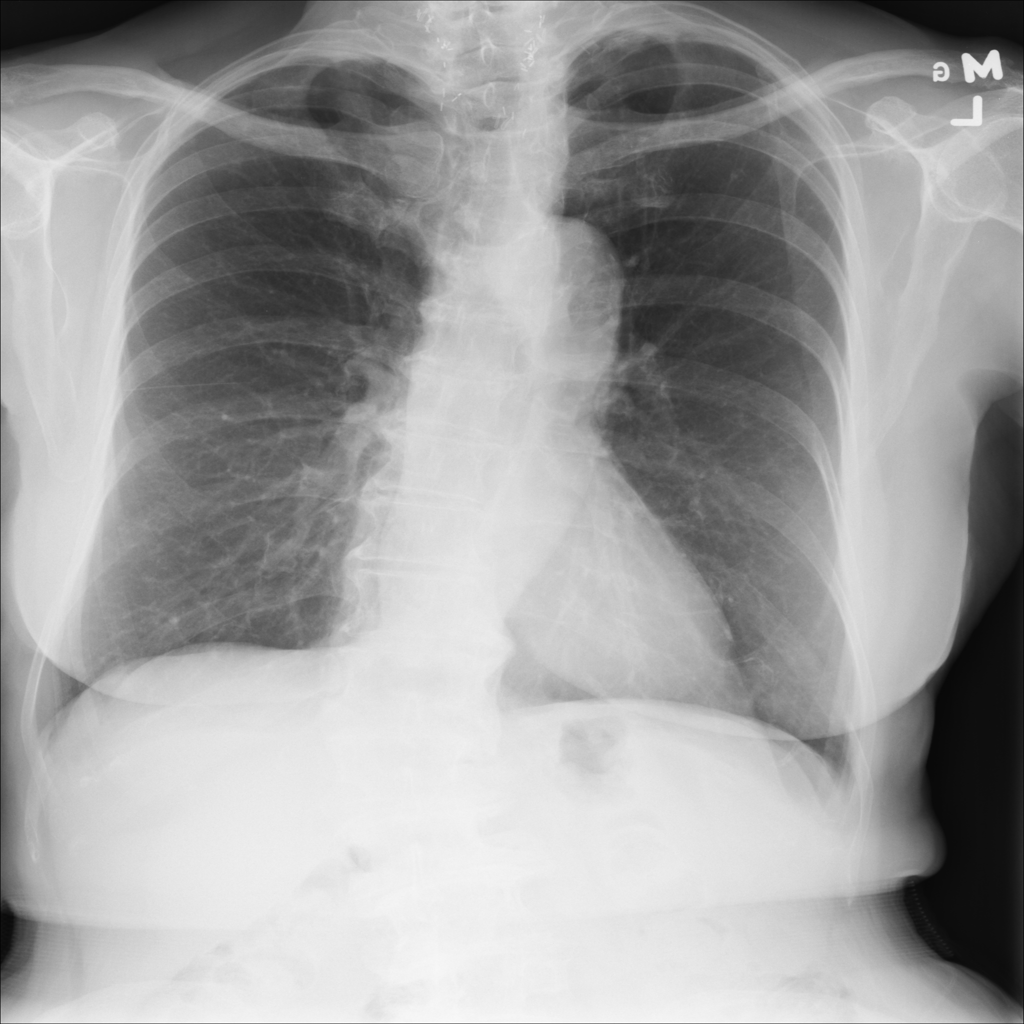

PAT-0E82 · IMG-000Emphysema

PAT-0E82 · IMG-000

AP